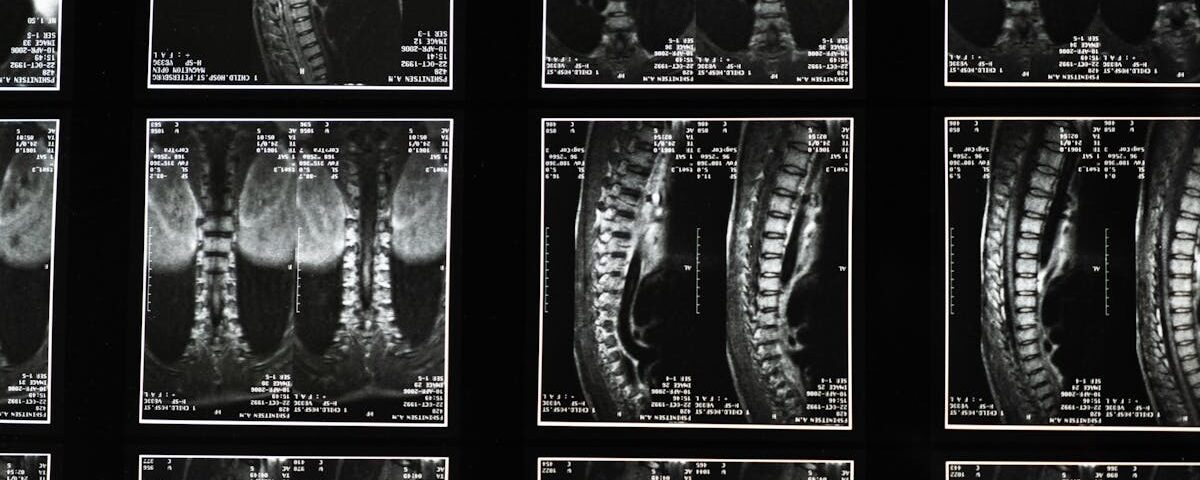

Une IRM ou une radiographie est généralement nécessaire pour confirmer la cause de la sciatique.